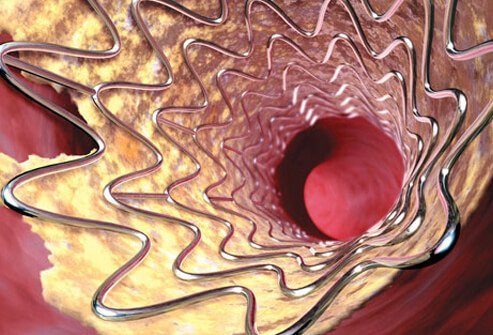

Preventing Another Stroke: Balloon and Stent

Some doctors also treat plaque-narrowed carotid (and occasionally other brain arteries) with a balloon on the end of a narrow catheter. Inflating the balloon pushes plaque aside and increases the vessel’s lumen (opens up the vessel). This opened artery then is reinforced (kept open) by an expandable stent that, when expanded, becomes rigid.